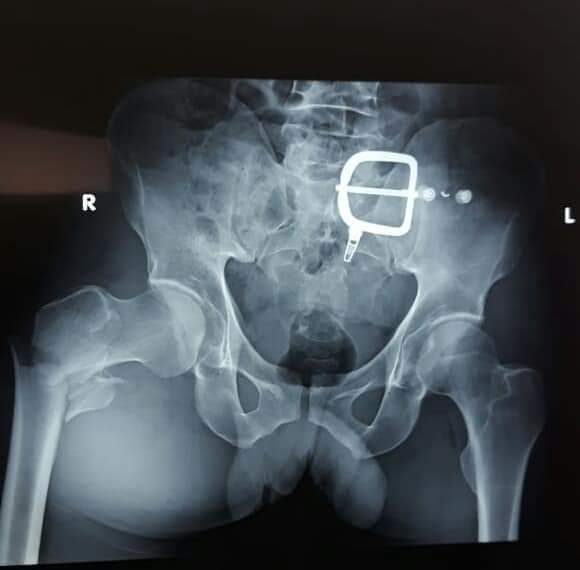

وأجريت هذه العملية تحت رئاسة الطبيب الجراح “البشيري محمد” اخصائي في جراحة العضام لفائدة مريض يبلغ عمره 55 سنة مصاب بكسر على مستوى الفخد الأيمن (Fracture pertrachanterienne ).

وعمل الطاقم الطبي على تثبيت الطرف العلوي من عضم الفخد جراحيا بواسطة مسمار غاما ( clou gamma ) لفائدة المريض.